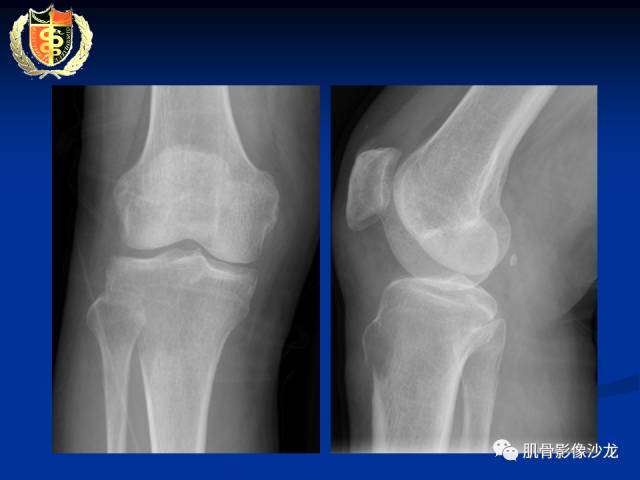

骨淋巴瘤及软骨肉瘤两例CT及MR影像表现

胫骨近端骨质破坏,边缘不清,破坏边模糊,骨皮质不完整,可见软组织肿块突破骨皮质外,病灶累及关节面下,无关节内累及,MRI病灶呈T2WI高信号,信号均匀,考虑:恶性肿瘤性病变,淋巴瘤先考虑,转移瘤及其他待排